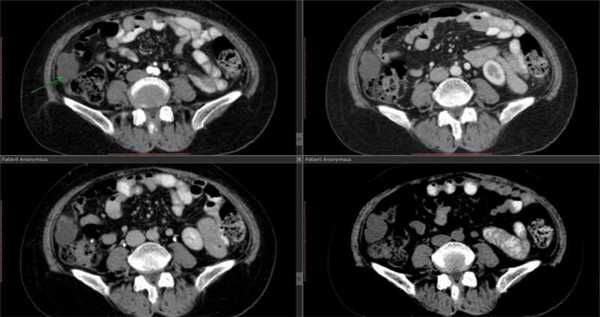

Radiology department of the Rijnland Hospital Leiderdorp and the University Medical Centre Groningen, the Netherlands.КТ-ангиография сосудов брюшной полости

КТ-ангиография сосудов брюшной полости считается одним из наиболее современных методов определения состояния здоровья сосудистой системы в указанной области. Его главным отличием выступает привлечение специального контрастного вещества.

Обычное ультразвуковое исследование не способно предоставить развернутую картину по структуре и общему состоянию сосудов в брюшной области, что способствовало разработке и внедрению технологии ангиографии. Вместе с контрастом получается визуализировать абсолютно все участки сосудистого русла. На основе полученной визуализации доктор сможет определить не только строение больших и мелких сосудов, но также выявить возможные аномалии в близлежащих органах.

Детализированная картина помогает обнаружить даже малейшие просветы, либо выявить внутренние образования, будь то онкологические опухоли или обычные тромбы. Причем изображение настолько подробно, что опытный рентгенолог способен на его основе распознать только-только зарождающиеся заболевания. Особенно актуален поиск недугов на начальной стадии развития для онкологических заболеваний.